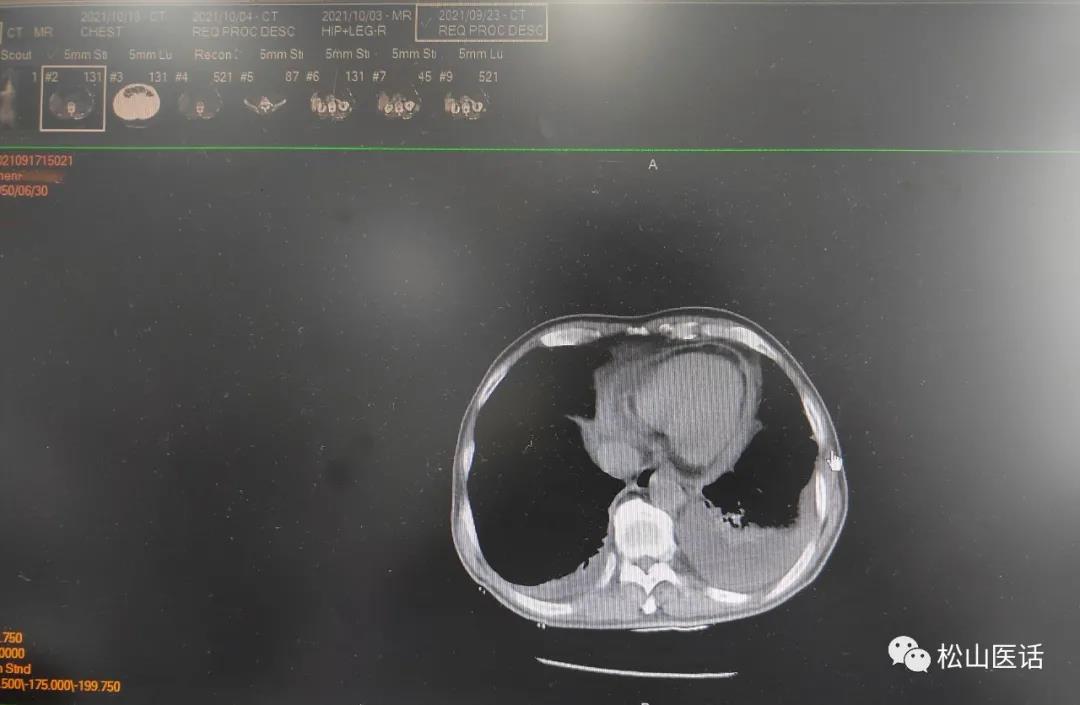

于是在10月4号复查了肺部CT以明确肺部感染的可能性,因为之前的肺部感染CT影像并不典型也不明显,只是报告有少量的胸腔积液。

2021-09-23CT报告

难道是肺部感染加重了?肺部CT的复查结果显示:

10月4号与9月23号比较没有明显改善,双侧胸腔少量积液但以左侧较多。